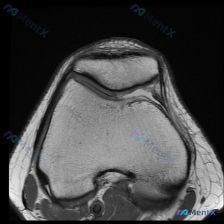

只给了一张膝关节T1轴位MRI怀疑软骨异常,你会怎么分析?

刚看到这个病例,是临床怀疑膝关节软骨异常,只提供了一张膝关节髌股关节层面的轴位T1加权MRI,整理一下分析思路分享给大家。

本次仅提供单张膝关节MRI轴位T1序列影像,临床核心疑问是评估是否存在软骨异常,未提供患者病史、症状及其他临床资料,也未提供其他序列/切面的MRI影像。

- 骨骼结构:髌骨形态完整,皮质连续,骨髓腔内信号正常;股骨远端滑车沟形态完整,皮质轮廓清晰,没有明显骨赘增生或骨缺损

- 关节软骨:髌骨后方关节面和股骨滑车沟软骨厚度均匀,轮廓平整,没有看到明确的软骨丢失、缺损或变薄

- 其他结构:髌股关节对位良好,没有脱位半脱位;关节腔内没有明显积液;周围支持带、肌腱结构形态正常,没有明显肿胀或异常信号;骨髓信号也没有异常改变

针对「软骨异常」这个关注点,现有影像的结论是:在当前这张T1轴位像上,没有看到明确的软骨异常征象。但这里必须强调:T1序列本身对软骨病变的敏感度很低,不能排除病变存在。